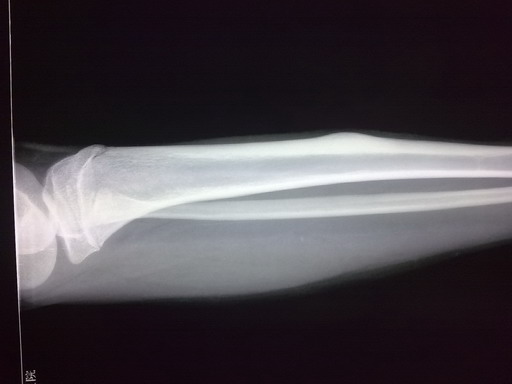

女孩,14岁,小腿疼痛一周,局部隆起,质硬,无红肿热痛

你侧胫骨中段见块状骨性突起。边缘清,并见硬化。考虑骨软骨瘤。

胫骨骨干皮质梭形增厚,虽无瘤巢,也考虑骨样骨瘤,原因不明,可能与感染有关,服用水杨酸制剂看看。

鉴别:骨化性纤维瘤、骨瘤、慢性骨膜下脓肿。

你侧胫骨中段见块状骨性突起。边缘清,考虑骨样骨瘤

左胫骨中段内前方骨皮质梭形增厚,髓腔未见累及,无骨膜反应。考虑良性病变。我考虑1低毒感染。

2骨样骨瘤:骨硬化较重,可能包埋了“瘤巢”。不象的地方就是病史不太支持:病程比较短,症状比较轻。试服用水杨酸制剂看看。

侧胫骨中段见块状骨性突起。边缘清,并见硬化。考虑骨软骨瘤。

考虑左胫骨中段骨样骨瘤。

左胫骨中段骨样骨瘤可能。隔期观察。

考虑 左胫骨中段骨样骨瘤。

考虑骨样骨瘤。病灶内部结构显示不清,请调调ct窗宽窗位。